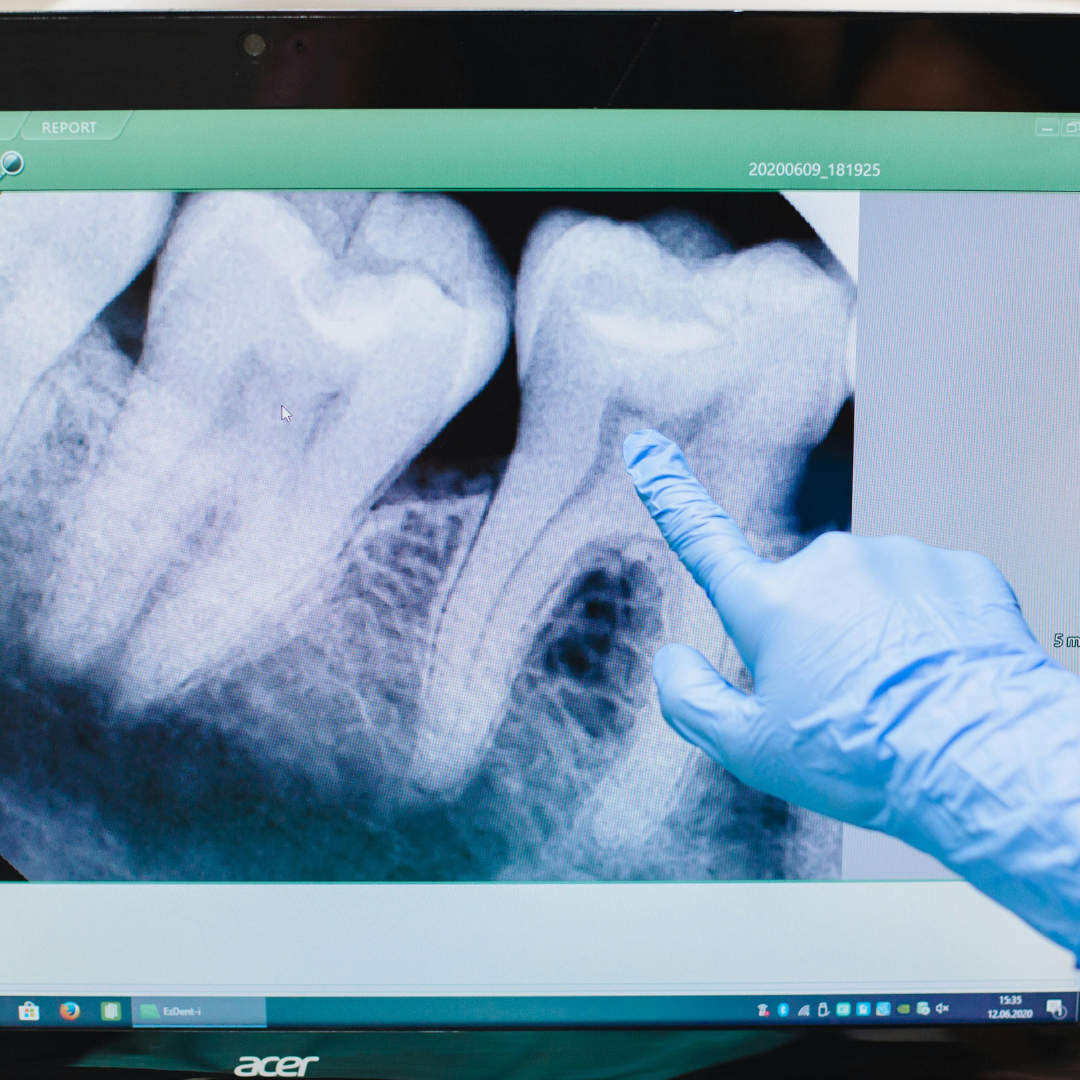

Digital X-Rays

State-of-the-art digital X-ray technology providing immediate, high-quality images with significantly reduced radiation exposure for safer dental care.